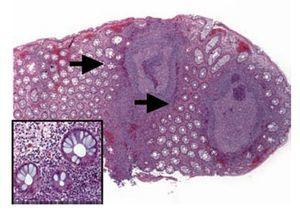

The patient, a 26-year-old woman, she was born in Mexico City without family history of IBD. She was referred to the hospital with a five months history of diarrhea with blood and blood watery stools. A colonoscopy and biopsy (Figure 1) confirmed ulcerative colitis (UC). Her symptoms were controlled after treatment. At the time of the diagnosis her marital status was single and she got married two years later. Currently she is under medical treatment for UC and she did not develop any complications related with UC. Her husband a 29 years old man born in Mexico City as well as his parents, but their grand parents came to Mexico from Spain. He was well for three years after he get married when he presented abdominal symptoms and the diagnosis of duodenal ulcer, tubulovillous colonic polyps, hepatic steatosis and hypercholesterolemia were made. One year later he developed diarrhea with blood. A colonoscopy and biopsy confirmed UC and no polyps (Figure 2) At the present time he is under treatment for UC and also for gastroesophageal reflux disease. He did not develop any complications related with UC.

Figure 1. Biopsy of rectum has altered architectural pattern and lymphoplasmocitary infiltration (arrow). In other areas are nodular lymphoid hyperplasias with germinal center (inset), diminution of mucous production and Paneth cells metaplasia (arrow head)